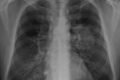

Mulher que fumava desde os 8 anos larga cigarro após descobrir câncer Ouvir 30 de agosto de 2023 Fumante desde os 8 anos de idade, Elcina da Silva Soares, 75 anos, descobriu um tumor no pulmão em fevereiro deste ano. Foram 67 anos fumando ininterruptamente até receber o diagnóstico de câncer de pulmão e decidir que nunca mais tocaria em um cigarro. Nascida em Orizona, cidade a 137 km de Goiânia (GO), Elcina conta que fumava para afastar o medo. Quando criança, ela e o irmão mais novo iam ainda de madrugada para a plantação de arroz da família para garantir que os pássaros não comeriam a colheita. “A gente acordava para cuidar da plantação, se não os passarinhos comiam tudo. Nós ficávamos com medo de ficar naquele lugar e fazíamos fogo, um lanchinho, fumávamos. Naquela época, era fumo de rolo”, recorda. Leia também Saúde Câncer de pulmão: saiba sinais da doença que matou Aracy Balabanian São Paulo Paciente com câncer em SP é primeiro a fazer autotransplante de pulmão Saúde “Descobri um câncer no pulmão aos 50. Nunca tinha fumado”, diz médica Mundo Câncer de pulmão: novo remédio reduz risco de morte em 51% Desde então, o cigarro está presente em sua vida. Já adulta, Elcina fumava aproximadamente uma carteira de cigarros por dia. “No fim de semana, quando eu bebia, fumava três, quatro, até mais carteiras porque quando a gente está bebendo, é acendendo um cigarro no toco do outro”, lembra. “Tive muita vontade de parar, mas o cigarro fazia parte da minha vida. Era triste, às vezes até toco de cigarro eu pegava das pessoas para fumar. Não tem coisa pior do que o vício”, afirma. Elcina da Silva Soares descobriu o câncer no pulmão em fevereiro deste ano. Desde então ela optou por largar o cigarro Tabagismo e câncer de pulmão O cigarro está associado a 90% dos casos de câncer de pulmão em todo o mundo. Ele também é considerado um fator de risco importante para doenças como o câncer de laringe, traqueia, faringe, tumores de cabeça e pescoço, enfisema pulmonar, bronquite crônica e demais problemas que afetam as vias aéreas superiores. “Quando o paciente fuma por muito tempo, os cílios do pulmão vão endurecendo e perdem a função de filtragem”, explica a pneumologista Gilda Elizabeth, do Hospital Brasília Unidade Águas Claras. De acordo com a médica, o tabagismo na infância traz riscos adicionais, uma vez que ele pode levar à inflamação dos brônquios, tornando a criança mais suscetível a infecções virais e pneumonias. “Ela fica com o sistema imunológico mais comprometido”, afirma a pneumologista. Na maioria dos casos, os sintomas acabam sendo silenciosos até que o quadro já esteja avançado. Para Elcina, foi uma febre causada pela infecção do coronavírus em fevereiro deste ano que fez os médicos descobrirem a doença. Uma tomografia dos pulmões mostrou a presença de uma massa que obstruía parte do brônquio. “Todos os médicos me disseram que se eu não tivesse tido Covid-19, morreria de câncer sem saber porque não senti nada. Um deles me disse ‘dona Elcina, a senhora teve a Covid-19 para te avisar do câncer de pulmão’”, lembra. ***desenho-câncer-de-pulmão O câncer de pulmão é o segundo mais comum em homens e mulheres no Brasil. De acordo com o Instituto Nacional de Câncer (Inca), cerca de 13% de todos os casos novos são nos órgãos Getty Images ***foto-câncer-de-pulmão No fim do século 20, o câncer de pulmão se tornou uma das principais causas de morte evitáveis no mundo Getty Images ***foto-câncer-de-pulmão O tabagismo é a principal causa. Cerca de 85% dos casos diagnosticados estão associados ao consumo de derivados de tabaco Getty Images ***foto-câncer-de-pulmão A mortalidade entre fumantes é cerca de 15 vezes maior do que entre pessoas que nunca fumaram, enquanto entre ex-fumantes é cerca de quatro vezes maior Getty Images ***foto-câncer-de-pulmão A exposição à poluição do ar, infecções pulmonares de repetição, doença pulmonar obstrutiva crônica (enfisema pulmonar e bronquite crônica), fatores genéticos e história familiar de câncer de pulmão também favorecem o desenvolvimento desse tipo de câncer Getty Images ***foto-câncer-de-pulmão Outros fatores de risco são: exposição ocupacional a agentes químicos ou físicos, água potável contendo arsênico, altas doses de suplementos de betacaroteno em fumantes e ex-fumantes Getty Images ***foto-câncer-de-pulmão Os sintomas geralmente não ocorrem até que o câncer esteja avançado. Porém, pessoas no estágio inicial da doença já podem apresentar tosse persistente, escarro com sangue, dor no peito, pneumonia recorrente, cansaço extremo, rouquidão persistente, piora da falta de ar, diminuição do apetite e dificuldade em engolir Getty Images ***foto-câncer-de-pulmão O diagnóstico do câncer no pulmão é feito com a avaliação dos sinais e sintomas apresentados, o histórico de saúde familiar e o resultado de exames específicos, como a radiografia do tórax, tomografia computadorizada e biópsia do tecido pulmonar Getty Images ***foto-câncer-de-pulmão Para aqueles com doença localizada no pulmão e nos linfonodos, o tratamento é feito com radioterapia e quimioterapia ao mesmo tempo Getty Images ***foto-câncer-de-pulmão Em pacientes que apresentam metástases a distância, o tratamento é com quimioterapia ou, em casos selecionados, com medicação baseada em terapia-alvo Getty Images ***foto-câncer-de-pulmão A cirurgia, quando possível, consiste na retirada do tumor com uma margem de segurança, além da remoção dos linfonodos próximos ao pulmão e localizados no mediastino. É o tratamento de escolha por proporcionar melhores resultados e controle da doença Getty Images Voltar Progredir 0 Tratamento e recuperação do câncer Dona Elcina passou por uma cirurgia em abril para a retirada do tumor, seguida por três sessões de quimioterapia, a última realizada este mês. A pneumologista Gilda Elizabeth vê o prognóstico da paciente com otimismo. “Mesmo com tanto tempo de tabagismo, a lesão era ressecável e ela ainda parou de fumar. Quando o paciente larga o cigarro, os sinais vitais, a pressão arterial, frequência cardíaca, oxigenação e inflamação nos brônquios melhoram”, afirma a médica. A aposentada se recupera bem. Ela passará por novos exames esta semana para avaliação dos pulmões e garante que não quer mais saber de cigarro. “Depois do diagnóstico, nunca mais fumei. O fumo não presta. É um vício horrível. Se pudesse voltar no tempo 60 anos, voltava para ter o meu pulmão limpinho, mas infelizmente não dá”, conta. Receba notícias do Metrópoles no seu Telegram e fique por dentro de tudo! Basta acessar o canal: https://t.me/metropolesurgente. Notícias